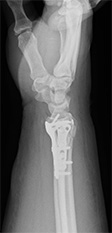

橈骨遠位端骨折(手首の骨折)

疾患と症状

転倒時に手をついて生じることが多い骨折です。

ずれが小さい場合は保存療法(ギブス固定)も可能です、ずれが大きい場合や早期のギブス除去、社会復帰を希望される場合に手術を行っております。

• 画像:橈骨遠位端骨折

(術前)